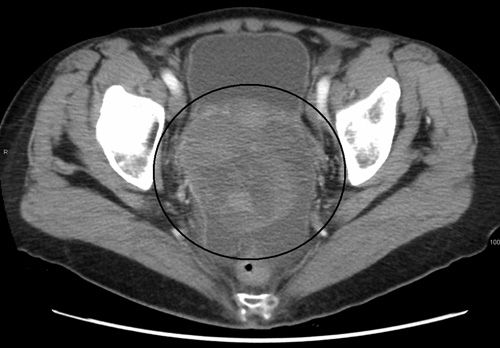

Ovarian cancer as seen on CT; source: James Heilman, MD, Wikimedia Commons